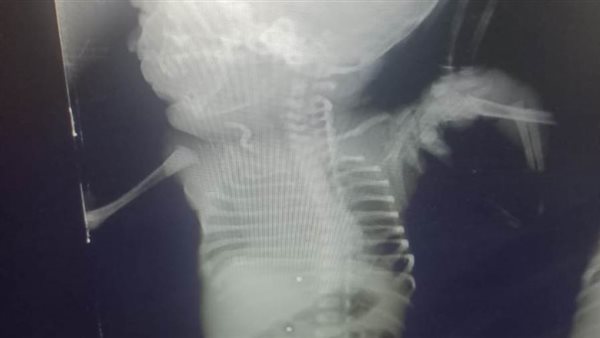

وأوضح الدكتور هاني جميعة وكيل وزارة الصحة بأنه تم استقبال الأم الحامل بقسم الطوارئ بمستشفى أبو حماد المركزي، بتشخيص مبدئي نزيف داخلي بالبطن، وهي في بداية الشهر التاسع من الحمل، مع اشتباه إصابة الرحم والجنين، وذلك نتيجة ادعاء تعدي من آخرين بطلق ناري "خرطوش" بالبطن مع وجود آثار لإصابات ظاهرية بالخرطوش، مع هبوط حاد بالدورة الدموية وانخفاض بضغط الدم، وبعد إجراء الفحوصات الطبية المختلفة، من موجات صوتية علي البطن والحوض والتحاليل اللازمة، تم التأكد من وجود نزيف داخلي بالبطن، وبعد مناظرة الحالة من أطباء النساء والتوليد وأطباء الجراحة العامة، تم حجزها بالقسم الداخلي ومنه إلى غرفة العمليات، للتدخل الجراحي العاجل، بعد الفحص الإكلينيكي للمريضة، حيث تم عمل استكشاف بالبطن، والذي أظهر وجود نزيف داخلي نتيجة اختراق الخرطوش لأمعاء المريضة، ليتم رتق الأمعاء، ووقف النزيف عن طريق أطباء الجراحة، هذا بالإضافة إلى إجراء عملية ولادة قيصرية، أظهرت اختراق الخرطوش لرحم الأم ووصوله إلي جسم الطفل، واستقرار عدد من طلقات الخرطوش بجسم الطفل من ناحية الظهر.